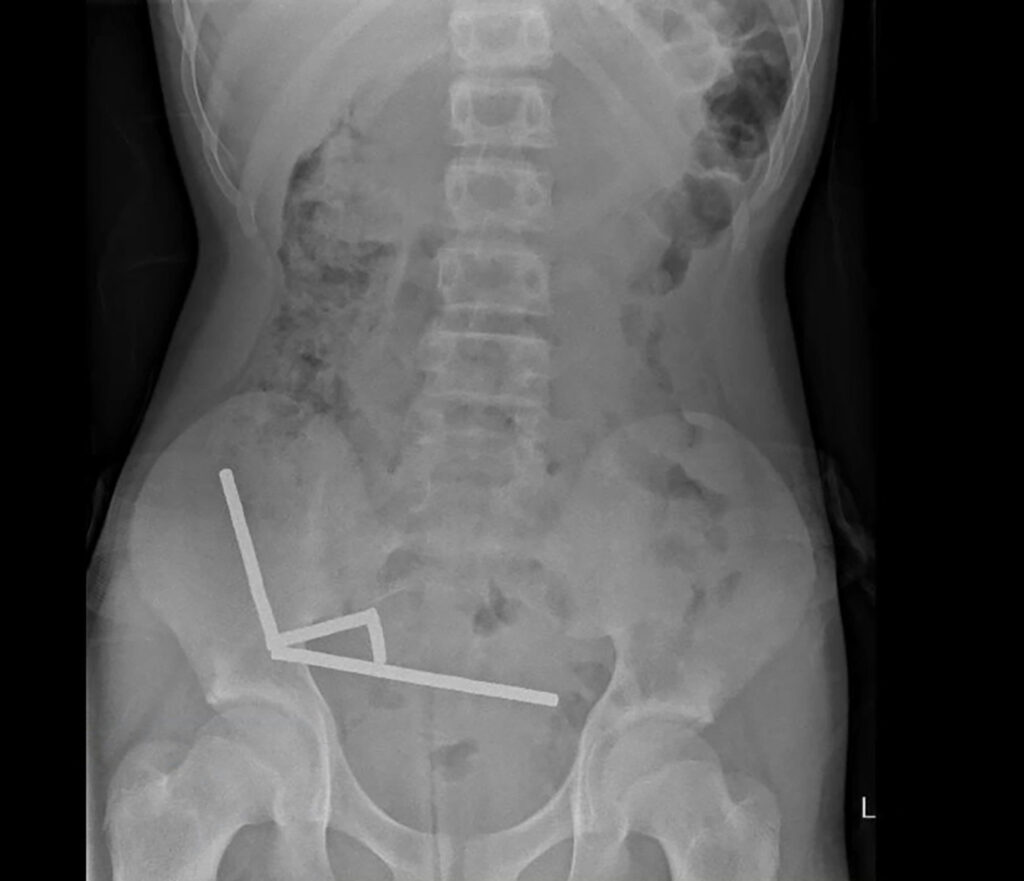

An X-ray revealed the magnets had clumped together into four straight lines inside the boy's intestines

An undated handout from the New Zealand Medical Journal shows an X-ray image of pieces of high-power magnets clumped up in the intestines of a New Zealand teenager in Tauranga.